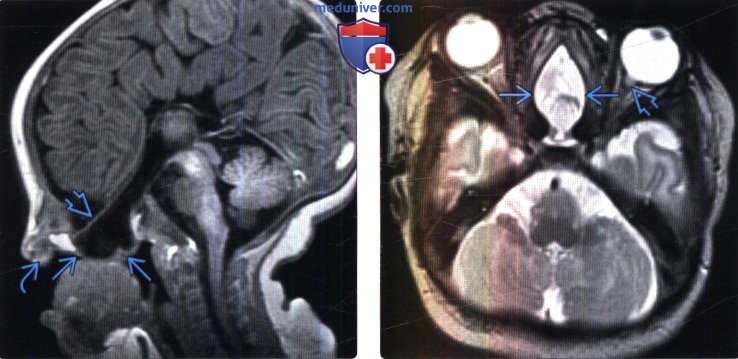

Внутричерепная гипотензия: КТ-исследования и их интерпретация

Раздел: Образы вокруг